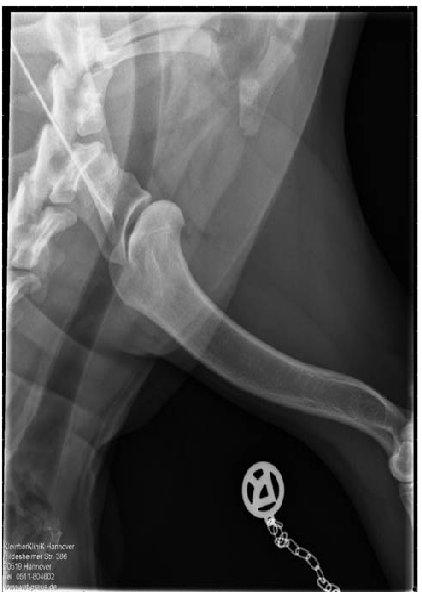

ED - OCD - Röntgenaufnahme